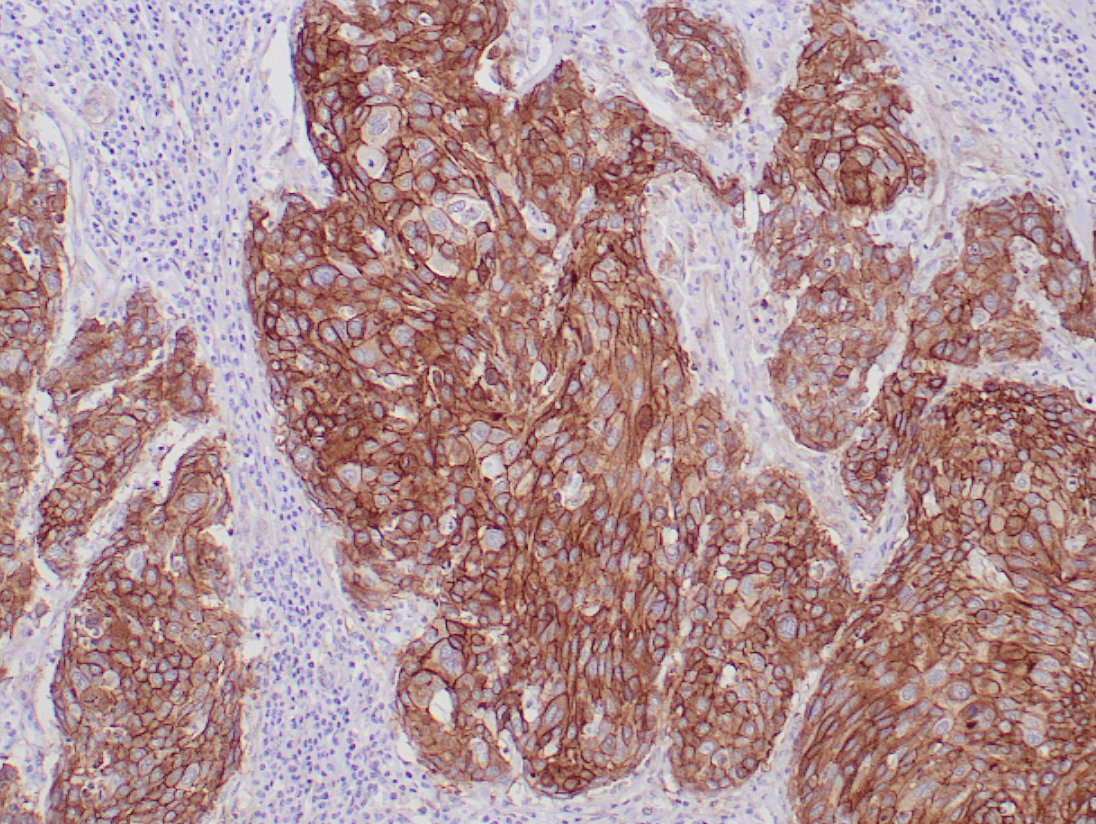

EGFR (PL-17)